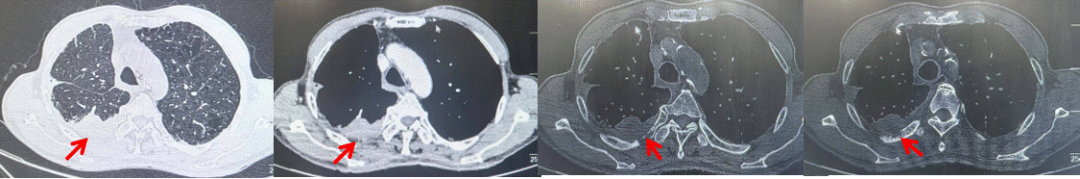

71岁男性,高血压病史20年,口服药物治疗,无糖尿病、心脏病等基础疾病,吸烟史50年,20支/天,已戒1年余,无饮酒史,无肿瘤家族史。2023.11因咳嗽、咳痰行胸CT检查:左肺下叶占位性病变,大小约12mmx8mm(如图5)。2023.11.20行“单孔胸腔镜左肺中下叶切除、肺门及纵隔淋巴结清扫、胸膜粘连松解术”;术后病理:(左肺下叶)结合免疫组化鳞状细胞癌(中、低分化),局部见脉管内癌栓,未见确切神经侵犯,(气管切缘)净。(淋巴结)未见转移癌0/19(4组0/1;5组0/1;6组0/2;7组0/1;9组0/1;10组0/2;11组0/3;12组0/2;13组0/2;14组0/4)。术后分期pT1bN0M0 IA期,术后定期复查。

图5:患者手术前(2023.11)胸部CT肺窗及纵隔窗

图6:患者胸膜及纵隔转移(2024.09)胸部CT肺窗及纵隔窗